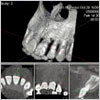

インプラントを希望された場合、あごの骨の厚みや質を分析するために、AICデンタルクリニックに完備していますCTスキャンによる術前・術後の撮影を必ず行います。

インプラントによる事故やトラブルを避けるためには、事前にCTによる診断が必要です。当クリニックではすべての患者様に対しCT撮影を行いインプラント治療に備えます。

今まで行われてきた、大きく切開、何針も縫い合わせるインプラント治療から脱皮し、切らない・縫わない、よって腫れない・痛まない術を行っています。患者様はその方が楽ですし、治癒も早くなります。そのためにはCTスキャンによる「3次元診断」が必須です。